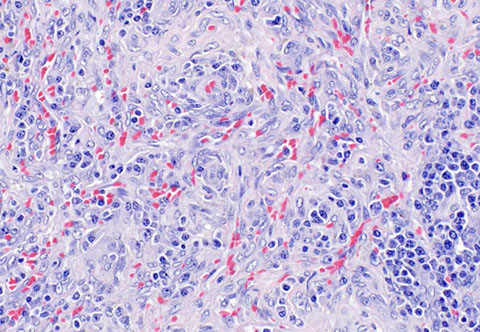

Splenic diffuse red pulp small B-cell lymphoma

Splenic diffuse red pulp lymphoma [5] - high power shows angulated cells